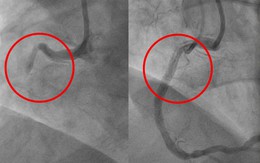

Bệnh nhân được theo dõi giấc ngủ bằng các thiết bị máy móc. Ảnh: TVBS.